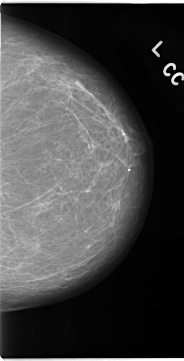

C_0155_1.RIGHT_CC

RIGHT_CC LINES 4720 PIXELS_PER_LINE 2328 BITS_PER_PIXEL 12 RESOLUTION 50 OVERLAY

FILE: C_0155_1.RIGHT_CC.OVERLAY

TOTAL_ABNORMALITIES 1

ABNORMALITY 1

LESION_TYPE MASS SHAPE OVAL MARGINS SPICULATED

ASSESSMENT 5

SUBTLETY 5

PATHOLOGY MALIGNANT

TOTAL_OUTLINES 1

BOUNDARY